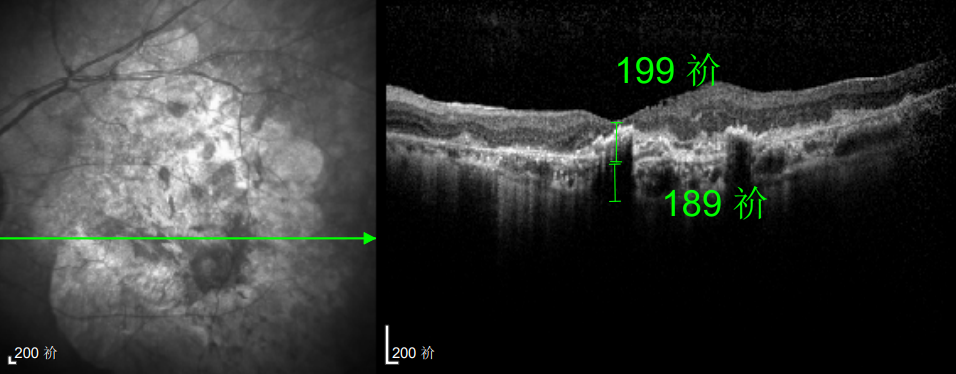

△延誤復查后的左眼

抗VEGF治療:規(guī)范隨訪,拒絕僥幸

這次教訓讓林婆婆徹底醒悟,此后她嚴格遵照王曉波主任的醫(yī)囑,定期隨訪、規(guī)范治療,再也不敢有絲毫懈怠。雖然左眼視力最終僅恢復至0.3,但穩(wěn)定的視力狀態(tài)讓她格外珍惜。